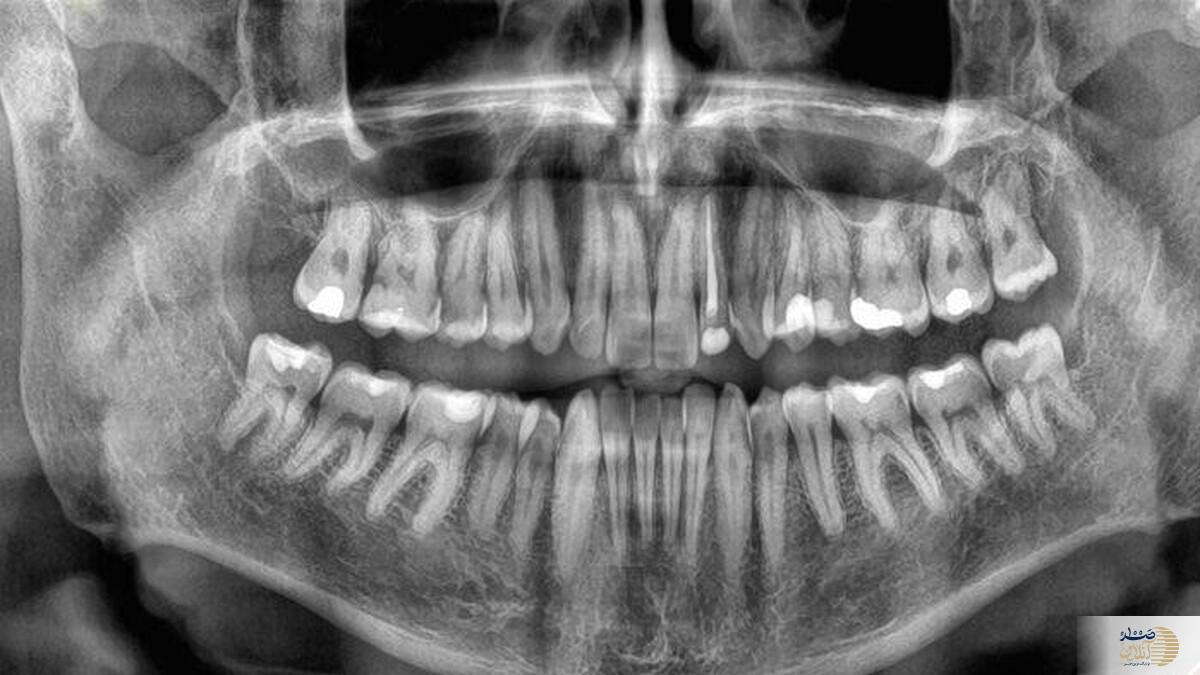

صد آنلاین | سرعت از دست دادن دندان‌ها در دوران سالمندی ممکن است با افزایش خطر مرگ در ارتباط باشد — این نتیجه‌ی یک مطالعه‌ی جامع تازه است که بر اهمیت سلامت دهان و دندان تأکید می‌کند و نشان می‌دهد افتادن دندان‌ها می‌تواند نشانه‌ای از وجود مشکلات جدی‌تر در سلامت عمومی بدن باشد.

به گزارش صد آنلاین ،  پیش‌تر نیز بین از دست دادن دندان و افزایش خطر مرگ زودرس ارتباط‌هایی گزارش شده بود — به‌طور کلی، هرچه فرد دندان‌های کمتری داشته باشد، احتمال مرگ زودتر بیشتر است. اما تا کنون هیچ داده‌ای درباره‌ی اینکه سرعت افتادن دندان‌ها چگونه می‌تواند این ارتباط را تغییر دهد، وجود نداشت.

برای یافتن پاسخ، تیمی از پژوهشگران دانشگاه سیچوان در چین، وضعیت دندان‌های ۸۰۷۳ سالمند را بررسی کردند و به‌مدت میانگین ۳.۵ سال، میزان افتادن دندان‌های آن‌ها را در ارتباط با نرخ مرگ‌ومیر پیگیری کردند.پژوهشگران در مقاله‌ی خود نوشتند «در میان افراد مسن، خطر مرگ ناشی از هر علت، به‌طور قابل‌توجهی با سرعت بیشتر از دست دادن دندان‌ها افزایش می‌یابد — فارغ از اینکه فرد در ابتدا چند دندان داشته باشد.»این رابطه حتی پس از در نظر گرفتن عواملی مانند جنسیت، سن، سطح تحصیلات، مصرف الکل و میزان فعالیت بدنی همچنان برقرار بود.

البته پژوهشگران تأکید می‌کنند که افتادن سریع دندان‌ها به‌خودی‌خود باعث مرگ نمی‌شود. بلکه مشکلاتی که منجر به افتادن دندان‌ها می‌شوند، ممکن است همان عواملی باشند که عمر فرد را کوتاه می‌کنند. بنابراین، از دست دادن دندان‌ها می‌تواند نشانه‌ای هشداردهنده از وضعیت کلی سلامت بدن و خطر مرگ زودرس باشد.سلامت دهان و دندان مدت‌هاست که با سلامت عمومی بدن مرتبط دانسته می‌شود و پیش‌تر نیز میان آن و بیماری‌هایی چون زوال شناختی و بیماری‌های قلبی ارتباط‌هایی گزارش شده است.با این حال، دلیل دقیق این ارتباط هنوز به‌روشنی مشخص نیست. پژوهشگران به عواملی مانند التهاب، رژیم غذایی نامناسب، چاقی و استرس روانی اشاره می‌کنند که می‌توانند هم بر افتادن دندان‌ها و هم بر سایر بیماری‌ها تأثیر بگذارند.

در مقاله آمده است:«اگرچه این توضیحات ارتباط میان افتادن دندان و عوامل شناخته‌شده‌ی خطر مرگ را نشان می‌دهد، اما مکانیسم دقیق این رابطه هنوز ناشناخته است و به پژوهش‌های بیشتری نیاز دارد.»پژوهشگران بر اهمیت مراقبت از دندان‌ها تأکید دارند.مراجعه‌ی منظم به دندان‌پزشک، مسواک زدن دوبار در روز، و ترک سیگار از مهم‌ترین عواملی هستند که سلامت دهان را حفظ می‌کنند — و تحقیقات پیشین نشان داده‌اند که همین عادت‌های ساده می‌توانند بر طول عمر سالمندان تأثیر بگذارند.هر دندانی که از دست می‌رود، احتمال مرگ را اندکی افزایش می‌دهد. به همین دلیل، بررسی منظم وضعیت دندان‌ها در ویزیت‌های دندان‌پزشکی می‌تواند ابزاری مفید برای ارزیابی خطر بیماری‌ها و مرگ در سالمندان باشد. همچنین، درمان‌های جایگزین مانند دندان مصنوعی می‌توانند کیفیت زندگی را بهبود بخشند.